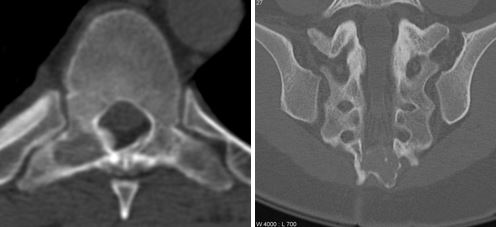

Остеоидная остеома |

Вид новообразования, который встречается примерно в 10% случаев всех опухолей позвоночного столба. Плохо диагностируется при рентгене, но четко определяется с помощью КТ и МРТ, хорошо поддается лечению и редко рецидивирует. |

Остеобластома |

Разновидность остеоидной остеомы, которая не вырастает более чем на 2 см, локализуется на задней части позвонков, обладает достаточно ярко выраженной симптоматикой и имеет склонность к появлению на тот самом месте. |